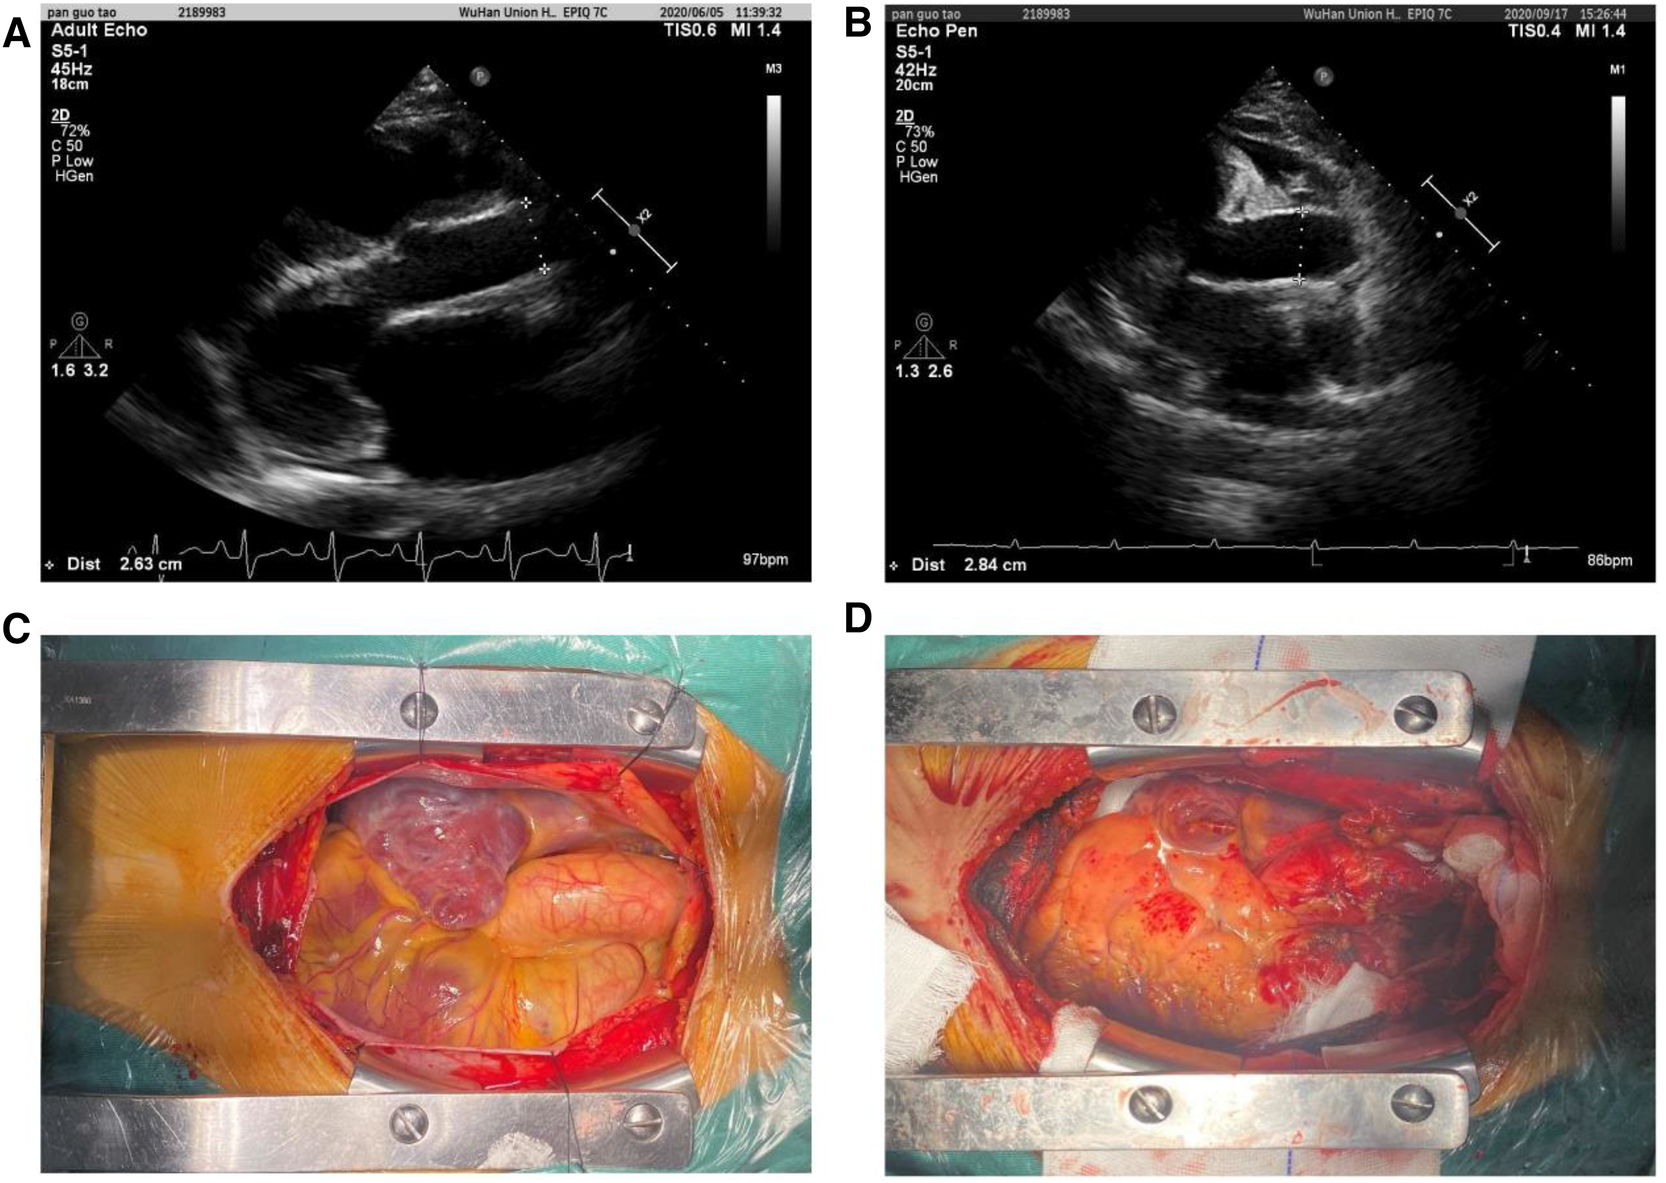

Our cohort incorporated all recipients of orthotopic heart transplantation at our institution from 1 January 2015 to 31 December 2018. A total of 361 patients were included, and all grafts were procured from donors after brain death. Patients who underwent cardiac retransplantation or multiorgan transplantation were excluded. Demographic and clinical characteristics of all heart transplant donors and recipients were collected retrospectively from electronic medical records, subsequent visits, or contact by our center. Preoperative echocardiography data were used to measure the recipient AAoD, and the donor AAoD was measured 3 weeks after operation (Figure 1). In this study, AAoD reflects the diameter of the ascending aorta 1 cm above the sinotubular junction (STJ). To obtain consistent data, we measured the AAoD at end-diastole using the leading edge-to-leading edge convention from the parasternal and suprasternal approaches by two-dimensional echocardiography.

Figure 1

Ascending aortic diameters measured using the leading edge-to-leading edge convention in preoperative (A, recipient) and postoperative (B, donor) by two-dimensional echocardiography. Intraoperative AAo image before heart removal (C) and AAo image after donor heart implantation (D).